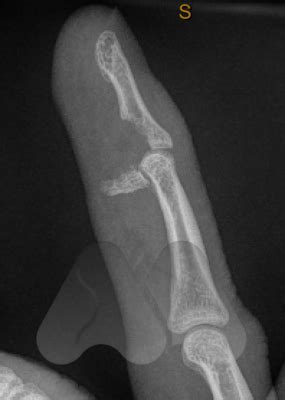

Jersey Finger Fracture - Jersey finger | Image | Radiopaedia.org / Treatment involves open reduction and internal fixation of the fracture fragment and then tendon.. Last updated february 02, 2021. Flexor digitorum profundus (fdp) avulsion. The ring finger is most commonly affected. Avulsion of flexor tendon from distal phalanx. Jersey finger (also known as rugby finger) is an avulsion of the flexor digitorium profundus tendon (fdp) from its distal insertion on the distal phalanx (zone i).1 2 3 the mechanism of injury is.

Look for avulsed fragments of distal phalanx fracture patterns are not reliable in predicting the level of tendon retraction A jersey finger is the injury of a finger tendon often caused during contact sports. The injury is common when one athlete grabs another player's jersey with the tips of one or more fingers while. Osseous fragment and avulsion of tendon from fracture. The flexor tendons of the hand play a very important role in functioning of the hand.

Large fracture which limits retraction to dip joint. A jersey finger is a rare hand injury that often affects athletes, especially those in sports that involve how do you suffer a jersey finger injury? Finger fractures are the most common types of fractures seen in primary care settings. A jersey finger is the injury of a finger tendon often caused during contact sports. Fdp retracts to level of pipj. Following the injury, the fingertip cannot be flexed (bent down) and the tendon can often be felt in the finger or the palm. Finger fractures may be caused by blunt trauma, hyperextension, hyperflexion, or twisting forces. There are 2 flexor tendons for each finger (excluding the thumb), both originating in the volar aspect of the forearm, each inserting onto.

Large fracture which limits retraction to dip joint. Pathophysiology of jersey finger injury. There are 2 flexor tendons for each finger (excluding the thumb), both originating in the volar aspect of the forearm, each inserting onto. An athlete can suffer this injury trying to tackle an opponent. A jersey finger is the injury of a finger tendon often caused during contact sports. Large avulsion fracture limits retraction to the level of the dip joint. This injury often occurs in american. Jersey finger occurs mainly during football and rugby. We then discuss different treatment options for jersey finger. Fractures of the middle phalanx. Inability to actively flex dip joint. Finger fractures are the most common types of fractures seen in primary care settings. Treatment involves open reduction and internal fixation of the fracture fragment and then tendon.